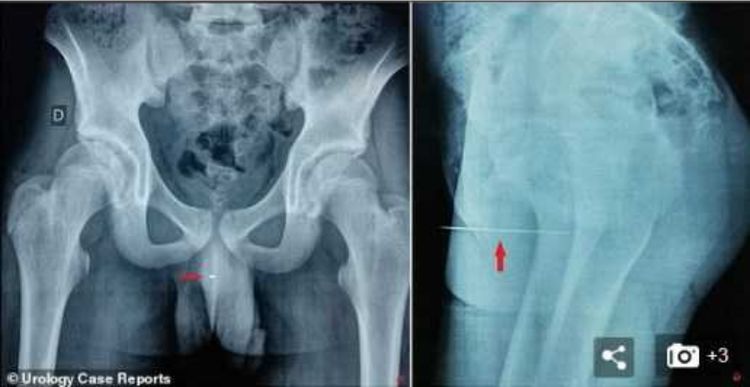

就在前段时间突尼斯某家医院又迎来了一位奇葩事情,十四岁小男孩有三天没有正常排尿了,下面很痛,医生就先让病人拍个片检查一下,当医生看到X光片的时候,医生都被眼前的一幕吓傻了,X光上面显示男孩的尿道里面有一根长达九厘米的缝衣针,据该男孩说当时只是为了好奇和得到快感才做出这样的事情。

在医生的帮助下,在小男孩的尿道5厘米处找到了那根9厘米的缝衣针的位置,然后对小男孩用了全身麻醉用镊子把针给取了出来,这次的手术非常的顺利,男孩在第二天就能出院了,然而医院方面却觉得这个小男孩可能有特殊性癖好才做出这样的事情。